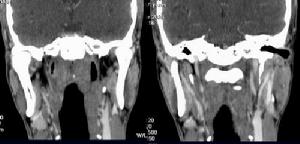

冠狀軸(二)面plane:按照軸線可將人體或器官切成不同的切面,以便從不同角度觀察某些結構。典型的切面有:矢狀面sagittalplane,是沿矢狀軸方向所做的切面,它是將人體分為左右兩部分的縱切面,如該切面恰通過人體的正中線,則叫做正中矢狀面mediansigittalplane;冠狀面或額狀面coronalplaneorfrontalplane,是沿冠狀軸方向所做的切面,它是將人體分為前後兩部的縱切面,與矢狀面和水平面相垂直;水平面或橫切面horizontalplaneortransverseplane,為沿水平線所做的橫切面,它將人體分為上下兩部,與上述兩個縱切面相垂直。須要注意的是,器官的切面一般不以人體的長軸為準而以其本身的長軸為準,即沿其長軸所做的切面叫縱切面longitudinalsection而與長軸垂直的切面叫橫切面transversesection。